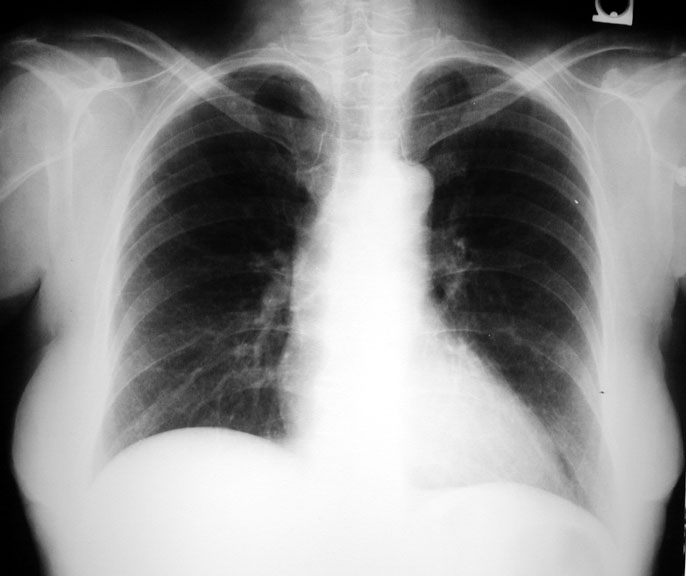

• Old film on left

Solitary pulmonary nodule in right mid lung field